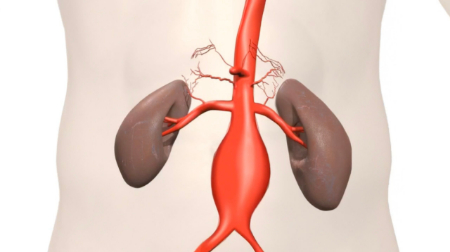

آنوریسم آئورت شکمی چیست؟

آنوریسم آئورت شکمی یک ناحیه بزرگ شده در قسمت پایین شریان اصلی بدن، به نام آئورت است. آئورت از قلب عبور کرده و از مرکز قفسه سینه و ناحیه شکم عبور می کند.

آئورت بزرگترین رگ خونی بدن است. پارگی آنوریسم آئورت شکمی می تواند باعث خونریزی تهدید کننده زندگی شود. درمان بستگی به اندازه آنوریسم و سرعت رشد آن دارد. درمان از چکاپ های سلامتی منظم و آزمایشات تصویربرداری تا جراحی اورژانسی متغیر است.

• آنوریسم های آئورت همچنین خطر ایجاد لخته خون در این ناحیه را افزایش می دهند. اگر لخته خونی از دیواره داخلی آنوریسم جدا شود، می تواند رگ خونی را در جای دیگری از بدن مسدود کند. علائم رگ خونی مسدود شده ممکن است شامل درد یا کاهش جریان خون به پاها، انگشتان پا، کلیه ها یا ناحیه شکم باشد.